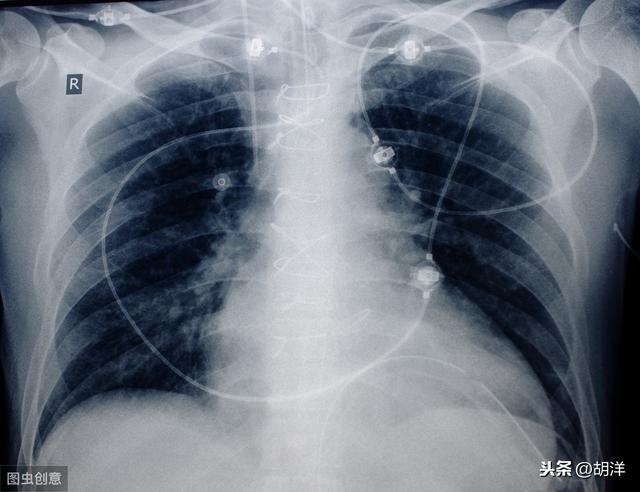

Dieser Patient war erst 39 Jahre alt, litt unter Engegefühl in der Brust und Kurzatmigkeit und wurde mit einem Adenokarzinom der rechten Lungenseite diagnostiziert, mit einem großen Pleuraerguss und Funktionsverlust der gesamten rechten Lunge. Ein so schwerwiegender Zustand ist bei älteren Menschen etwas häufiger, und wenn er nicht behandelt wird, kommt es bald zum Atemstillstand. Glücklicherweise spricht sie gut auf eine gezielte Therapie an und lebt nun seit mehr als drei Jahren mit dem Tumor, wobei ihr Pleuraerguss unter Kontrolle ist.